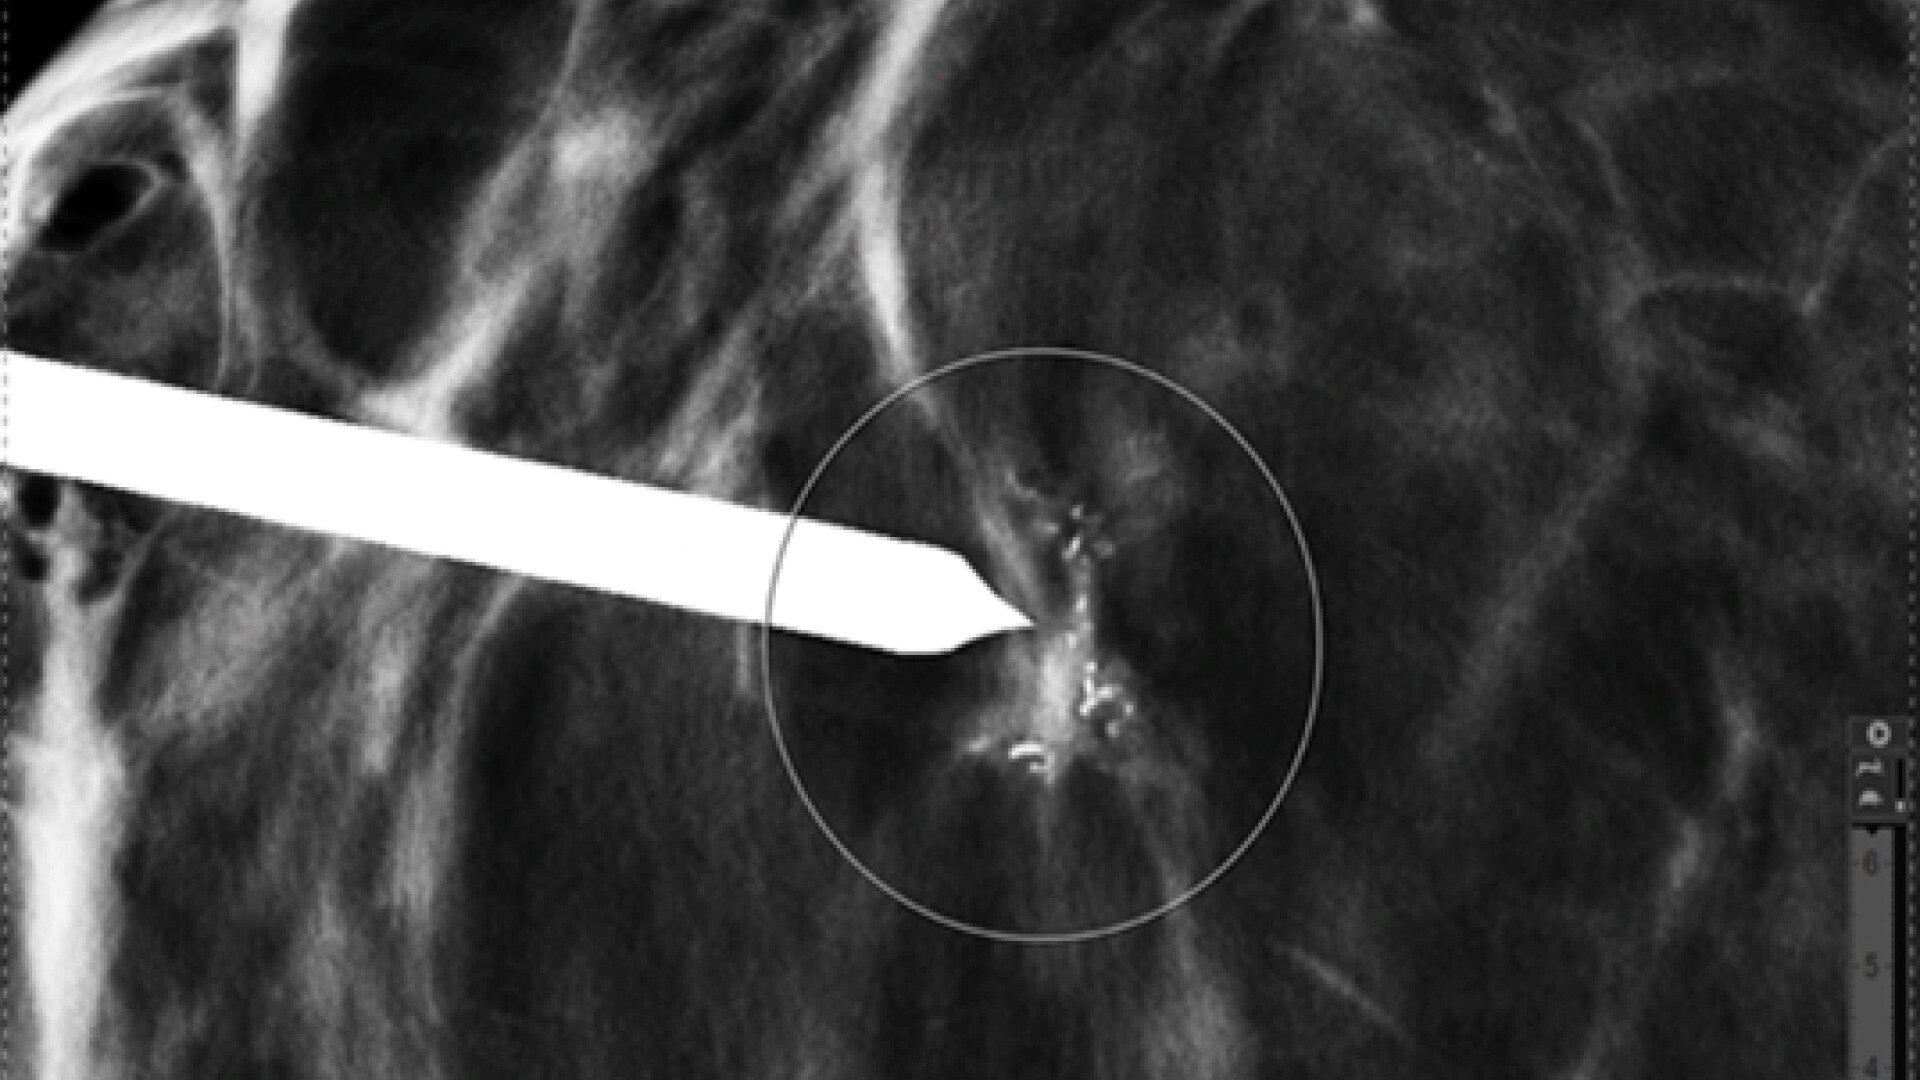

Discover the advanced capabilities of the SIGNA™ Architect, GE HealthCare's 3T magnet MRI system. Featuring a 128-channel Total Digital Imaging (TDI) receive chain and exceptional 44mT/m @ 200T/m/s gradient performance, this system sets a high standard for precision. Streamline your workflow effortlessly with products like AIR™ Recon DL, AIR™ Coils, and Sonic DL™, designed to enhance your diagnostic efficiency.

Reinforce your clinical confidence with the SIGNA™ Architect's AI-based applications, powered by Edison. Implement feet-first imaging for all exams, emphasizing a patient-friendly approach. The Effortless AIR™ Recon DL further enhances imaging efficiency, providing diagnostic precision to meet your high standards.

Stay at the forefront of medical imaging with the SIGNA™ Architect Lift, facilitating seamless updates to the latest technology. The dockable eXpress Patient Table adds operational flexibility to your practice. Explore advanced capabilities, including options for Radiation Oncology and Surgical Suite, aligning with the evolving needs of modern radiology.